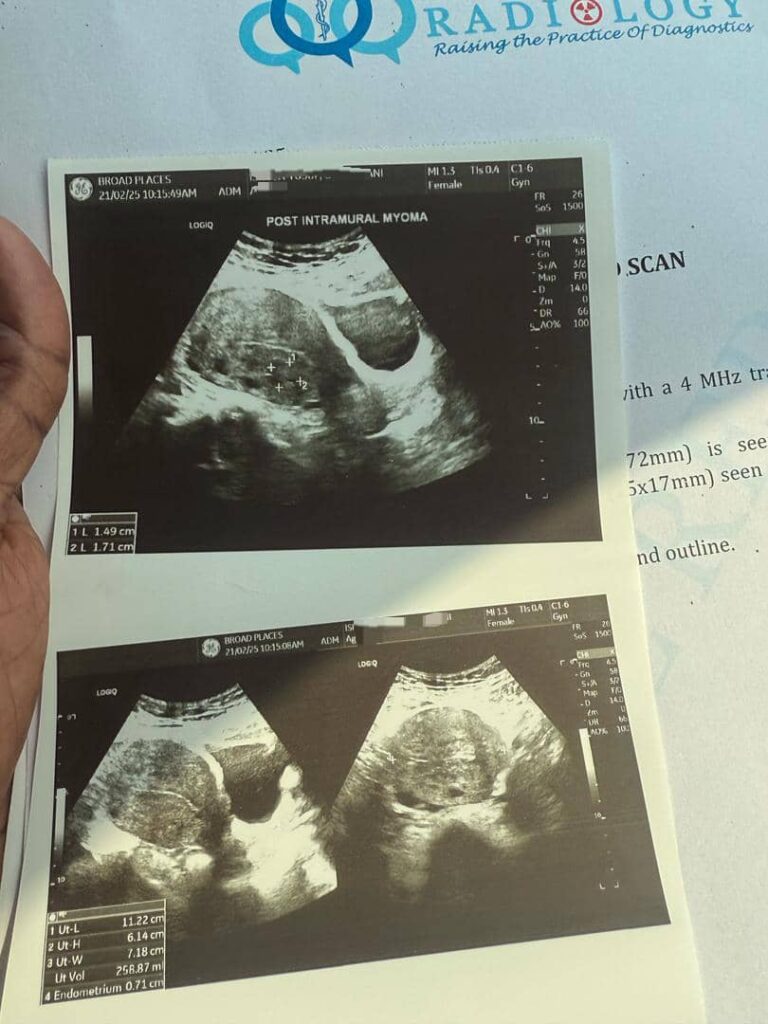

result from her scan

this is the outcome of using ultimate fibroid crusher for just two weeks

result from just 2 weeks of consistent use of ultimate fibroid crusher